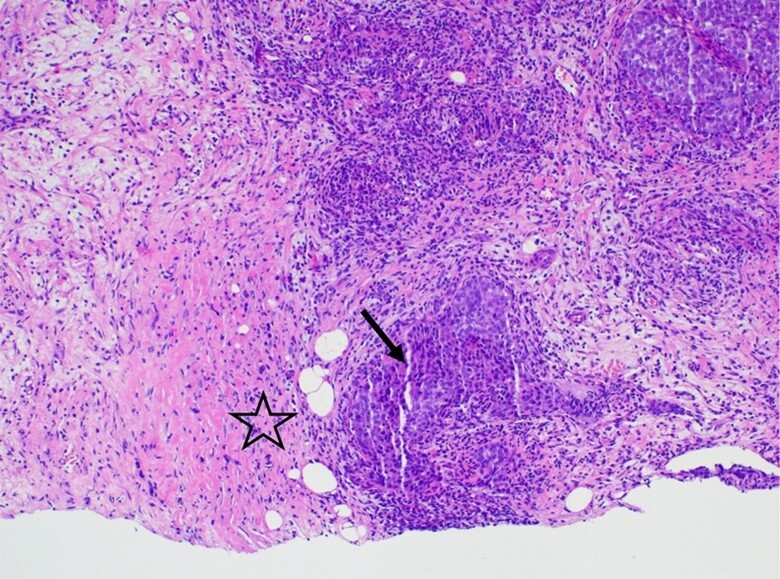

Neuroendocrine breast cancer (NEBC) is a rare and heterogeneous entity. It most commonly presents a luminal phenotype and a worse prognosis. When diagnosed in an advanced stage, metastasis from another neuroendocrine tumor should be excluded. This case features a premenopausal woman with an oligometastatic breast large cell neuroendocrine carcinoma, estrogen receptor (ER) positive, and human epidermal growth factor receptor 2 (HER2) negative. Since the patient was very symptomatic at the presentation of the disease, chemotherapy was started. Complete radiological response of the metastatic disease was achieved, and the patient was then submitted to radical breast surgery and bilateral oophorectomy. She subsequently underwent radiation therapy. Since then and to date, she has been under endocrine therapy (ET) and a CDK4/6 inhibitor (CDK4/6i), with no evidence of malignant disease. Evidence to guide the choice of treatment for these tumors is currently scarce. In cases with oligometastatic disease, radical treatment should be considered. Given that this entity is rare, its reporting should be encouraged.